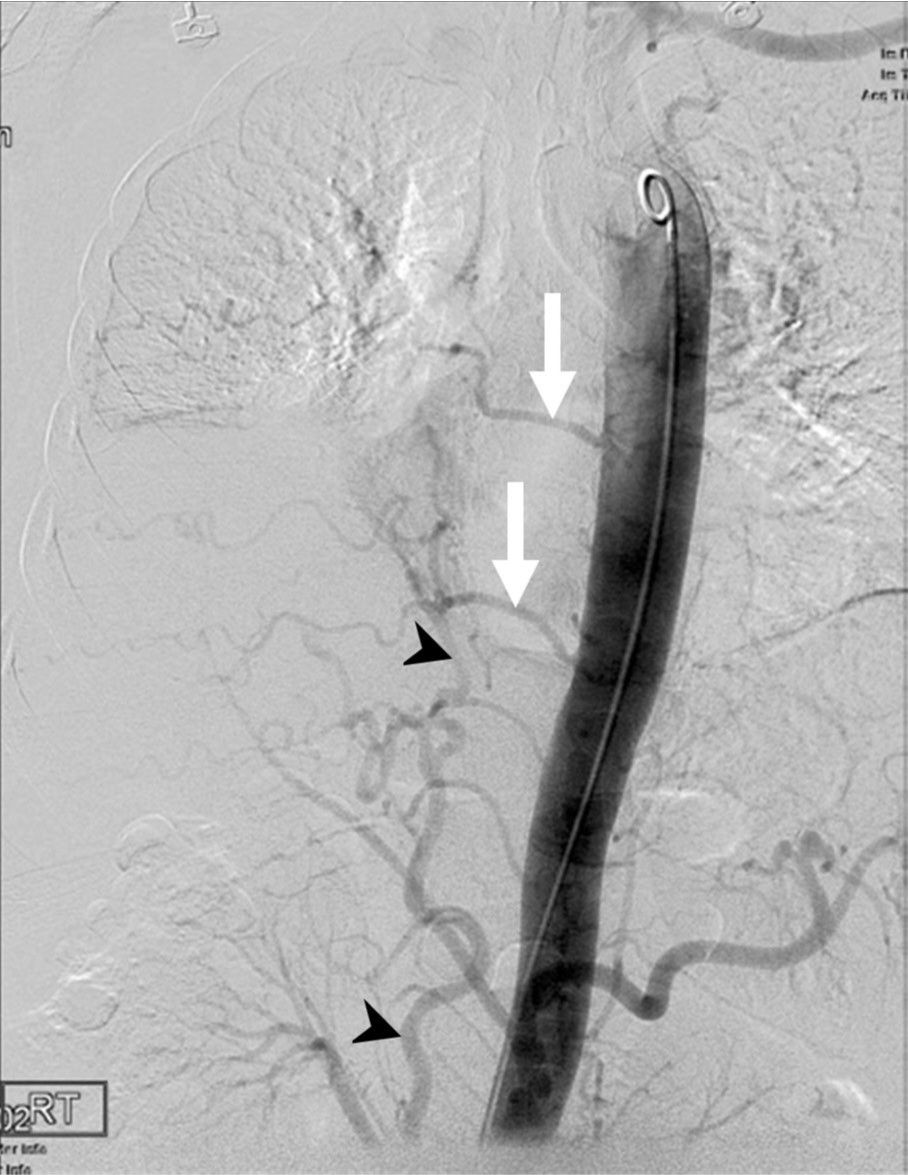

Fig. 1. A

Fig. 1A. Chest CT scan shows atelectasis of right middle and lower lobes (arrows).

Fig. 2.

Fig. 2. Thoracic aortogram shows no demonstration of the right bronchial artery and hypertrophy of the right inferior phrenic (arrowheads) and intercostal (arrows) arteries.

흉부 CT영상에서 우측 폐 중엽 및 하엽 기관지 내경 감소 및 anthracofibrosis가 의심되었고, 원위부 우중엽과 우하엽에 폐쇄성 무기폐 소견이 관찰되었으며 우기관지동맥이 우쇄골하동맥 근위부에서 기원하는 것으로 추정되었음(Fig. 1). 기관지내시경에서 우중엽에서 출혈이 관찰되었음.